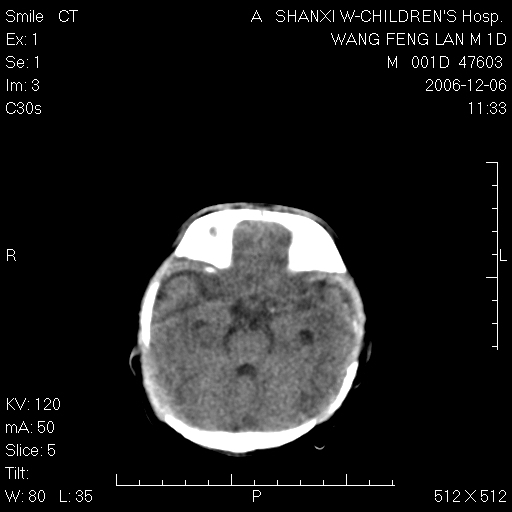

以下是引用husiling在2006-12-6 18:14:00的发言:[br]1\\hie[br]2\\蛛血.

以下是引用zjzjr在2006-12-6 19:29:00的发言:[br]支持新生儿缺血缺氧性脑病伴少量蛛网膜下腔出血.

以下是引用卜一在2006-12-6 21:38:00的发言:[br][br] 支持:新生儿缺血缺氧性脑病伴少量蛛网膜下腔出血 [br]